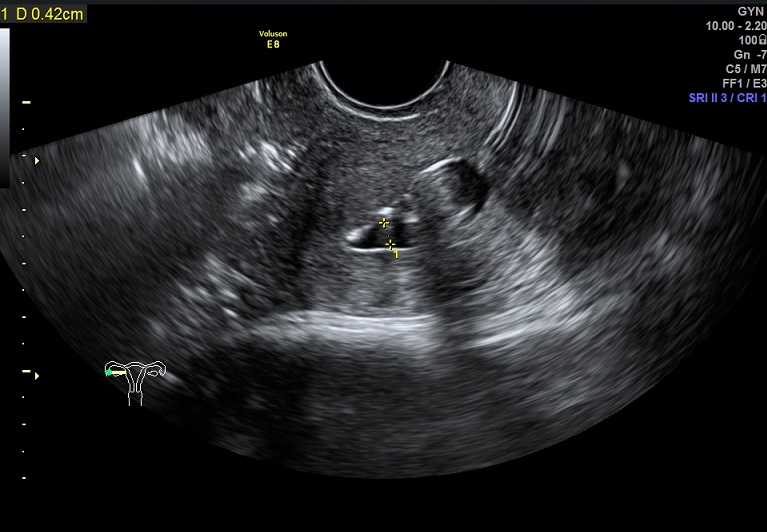

女性,27岁,原发性不孕2年。常规二维超声子宫及宫腔置管后水造影二维、三维均未发现明显异常。子宫输卵管实时三维超声造影显示:双侧输卵管走形柔顺自然,由宫角部延展而出,近端稍纤细,远端略粗大,造影剂从伞端溢出后环绕于卵巢周边,并可见盆腔内均匀弥散。诊断:双侧输卵管通畅